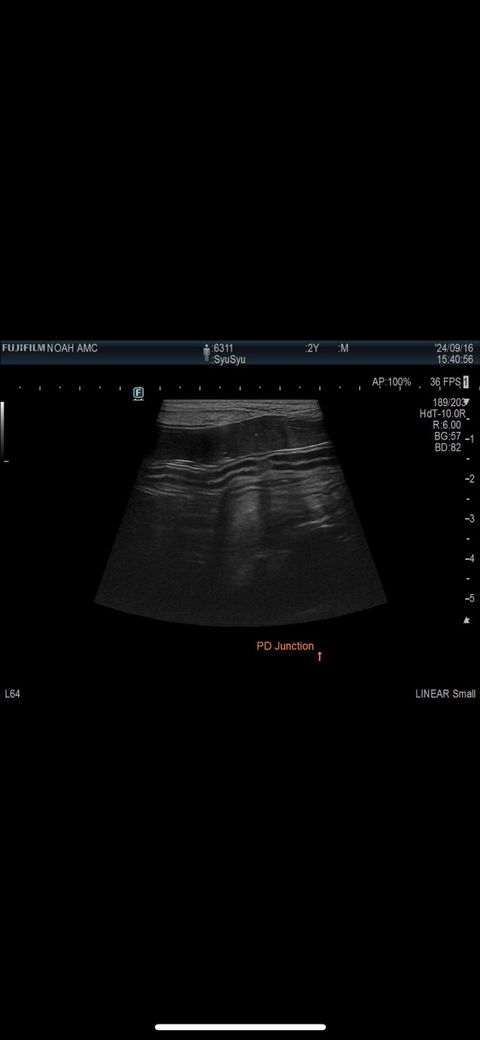

첨부된 사진에는 결장이 포함된 사진이 단한장도 없고, 있다고 하여도 초음파 검사는 정지사진으로는 별 진단적 의미가 없습니다. 초음파를 직접 본 영상의의 소견이 가장 중요합니다.